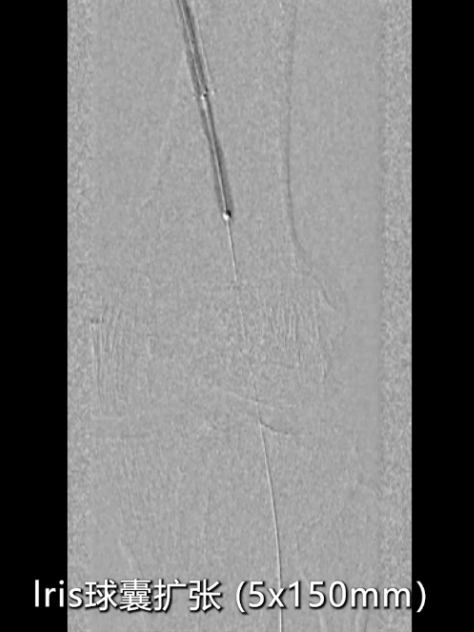

针对CT测量提示的股动脉远端及腘动脉段(直径约5mm),使用4×150mmRanger药物涂层球囊扩张;

近端支架内病变采用5×200mmRanger药物涂层球囊扩张,强化抗再狭窄效果。